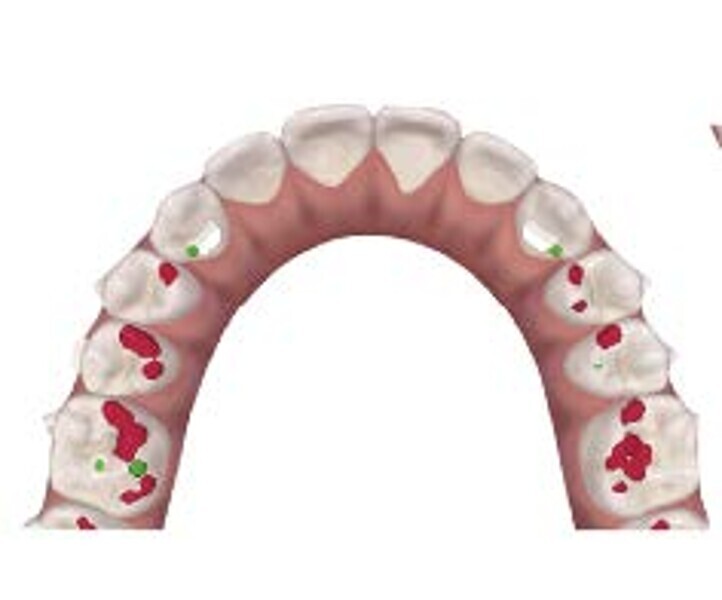

En raison de l’âge du patient, les aligneurs ont été changés tous les dix jours, dans le cadre d’un traitement d’une durée inférieure à six mois. À la fin de la première série d’aligneurs, un nouveau plan de traitement numérique comportant cinq autres aligneurs a été conçu, en vue d’améliorer l’intercuspidation des molaires sans élastiques. (Photos : Dr Alessandro Greco)

Le plan de traitement numérique (ClinCheck) avait prévu douze aligneurs pour l’arcade maxillaire et dix-sept pour l’arcade mandibulaire. Les objectifs du traitement visaient à combiner les mouvements verticaux d’extrusion des dents postérieures et les mouvements d’intrusion des dents antérieurs, au moyen de rampes d’occlusion, tout en utilisant des taquets d’extrusion pour assurer la désocclusion des dents postérieures et l’intrusion des dents antérieures inférieures, nécessaires au nivellement de l’arcade mandibulaire. La courbe de Spee a été nivelée et le profil plat ainsi que la position des lèvres ont été améliorés par une vestibulo-version des incisives supérieures et inférieures. Le plan avait prévu des élastiques de classe II pour faciliter la vestibulo-version des dents inférieures et les puissants contacts occlusaux postérieurs, avec une extrusion relative des dents postérieures. Une morphologie plus large de l’arcade et une intercuspidation idéale ont été obtenues par des mouvements de torque proches de 0° des dents latérales et postérieures supérieures. Aucune conception technique excessive n’avait été prévue dans le plan de traitement numérique. En raison de l’âge du patient, les aligneurs ont été changés tous les dix jours, dans le cadre d’un traitement d’une durée inférieure à six mois. À la fin de la première série d’aligneurs (Figs. 20–24), un nouveau plan de traitement numérique comportant cinq autres aligneurs a été conçu, en vue d’améliorer l’intercuspidation des molaires sans élastiques. La durée totale du traitement a donc été prolongée jusqu’à 7,5 mois puisque les aligneurs supplémentaires étaient changés toutes les semaines.